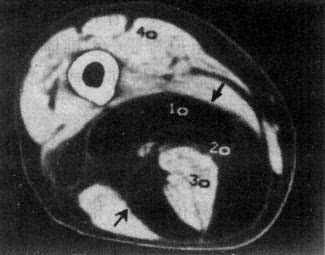

图2-2-1 大腿脂肪瘤

右大腿中1/3后内侧低密度肿块,境界清楚,CT值-100Hu